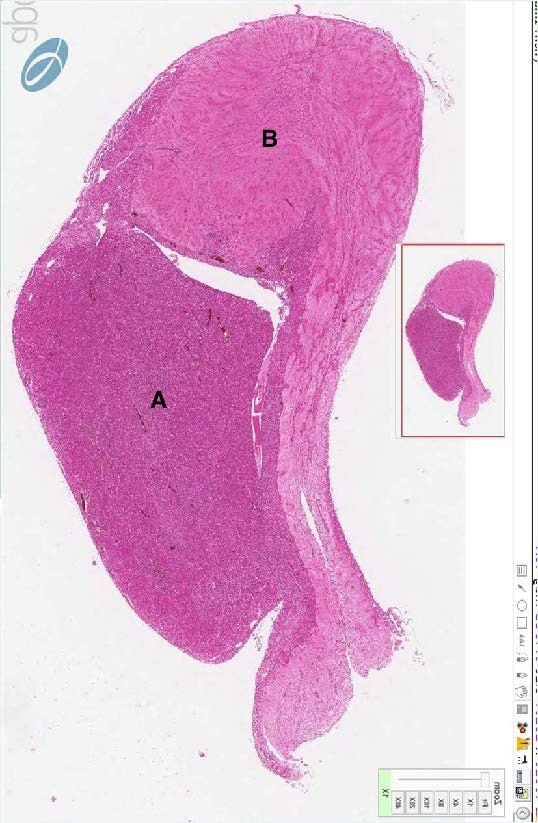

Which label represents the anterior pituitary in this H&E section of the pituitary gland? Which one represents the posterior pituitary?

A - posterior pituitary

B - anterior pituitary